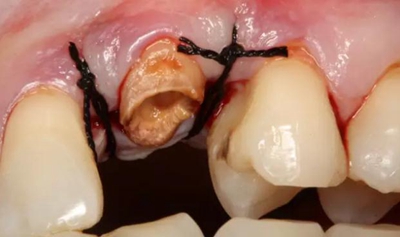

改良垂直褥式縫合關(guān)閉傷口,傷口無(wú)明顯滲血,高嵌體預(yù)備完畢后,硅橡膠取模,見邊緣清晰。灌注模型,模型上3MZ350XT分層堆塑高嵌體。

一周后拆除縫線,試戴高嵌體,試戴合適后雙固化粘結(jié)。調(diào)合,拋光。